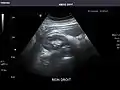

Aorta: Visualized portions normal in caliber, 16 x 15 mm.

Aorta